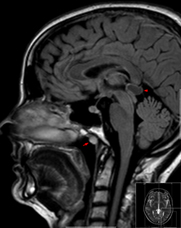

MRT

File:TornwaldZysteMRTFLAIRsag.png-WikimediaCommons

Beim MRT auch Kernspin genannt handelt es sich um eine magnetische Untersuchung. Die Zellkerne werden durch einen starken Magneten magnetisiert und geben bei der automatischen Entmagnetisierung eine magnetische Energie ab, die dann abgebildet wird. Jedes Gewebe entmagnetisiert unterschiedlich schnell und das ergibt unterschiedliche Graustufen auf dem Bild. Weichteile wie Bandscheiben oder Nerven lassen sich im MRT besser erkennen.

Magnetische Wellen sind nach heutigem Wissenstand unschädlich für den Körper und auch in der Schwangerschaft.